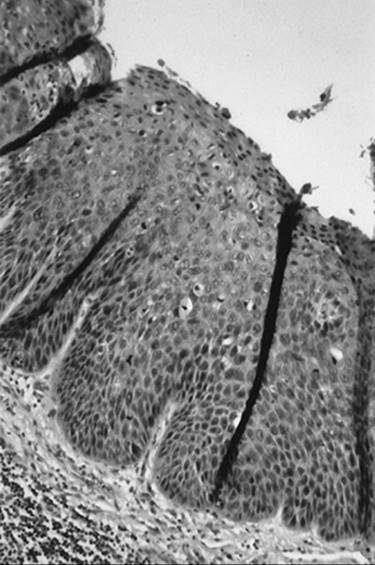

Verrucous Carcinoma

Verrucous carcinoma is a variant of squamous cell carcinoma with distinctive pathologic and clinical characteristics. It is characterized by a large condylomatous or cauliflower-like lesion with minimal cellular atypia, a pushing border, and rare metastasis. Unless biopsies are deep enough, it may be confused with benign condyloma or papilloma. Wide local excision is the preferred therapy. Radiotherapy is contraindicated given the potential for anaplastic transformation.